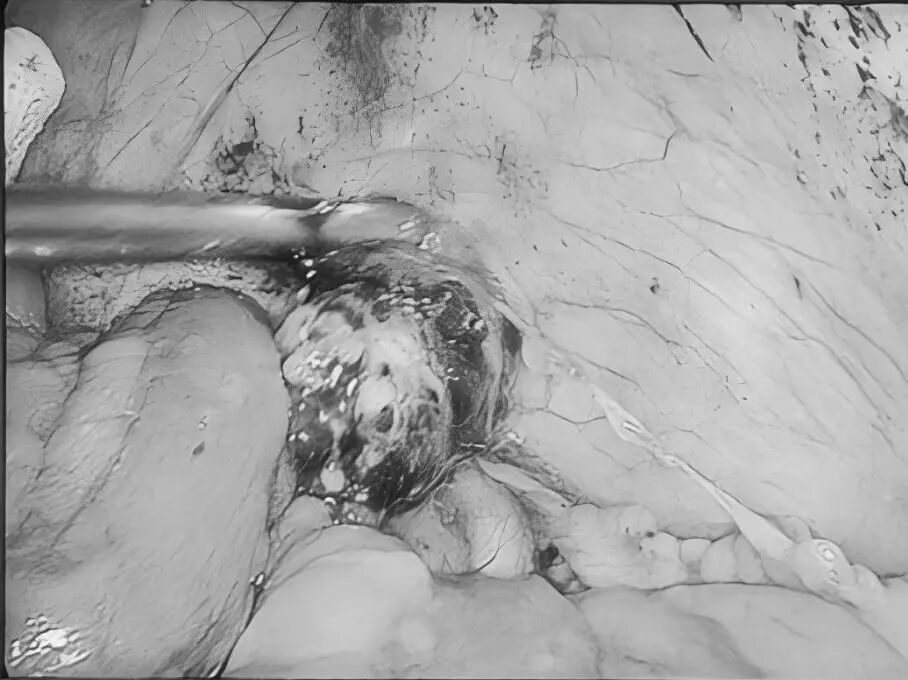

为深入践行人才强院核心战略,加速打造高水平医疗专家团队,引领学科跨越式发展,7月15日,贵州航天医院成功签约(柔性引进)知名肛肠外科专家高大勇教授,并举行“高大勇教授名医工作室”授牌仪式。贵州航天医院党委书记杨军,院长廖江荣,副院长彭亮、马庆庆、蒋婷出席仪式,普外科全体医护人员参加。 仪式上,杨军为高教授颁发了聘书,双方共同签署了合作协议,高教授授予普外科“名医工作室”函牌。 聘书颁发 柔性人才引进协议签约 名医工作室授牌 仪式后,高大勇教授前往科室开展早交班、教学查房等工作,针对疑难病例给予专业的治疗建议和科学指导。 此次柔性引进高大勇教授并设立名医工作室,将进一步促进贵州航天医院普外科在学科建设、技术创新、人才培养、科研教学等方面能力的提升,推动我院肛肠疾病诊疗能力实现跨越式发展,为广大患者带来优质医疗服务。 贵州航天医院普外科专家团队 高大勇 普外科(肛肠外科)学科带头人、名誉主任,主任医师、教授 临床擅长:对中西医结合诊治肛肠学科各种常见病、多发病及疑难杂症等具有丰富的临床经验。 原遵义市第一人民医院(遵义医科大学第三附属医院)、遵义市中医院肛肠科主任。中华中医药学会肛肠分会常委,全国中医肛肠学科名专家,中国健康促进与教育协会肛肠分会常委,中国康复医学会肛肠疾病康复专业委员会常委,中国民间中医医药研究开发协会肛肠分会副秘书长,中国医师协会中西医结合肛肠医师专业委员会常委,国家二级心理咨询师,贵州省第一批中医名医工作指导老师,遵义市名中医,遵义市肛肠学会会长,遵义市肛肠质控中心名誉主任,遵义市中西医结合学会名誉会长,遵义市健康科普专家,原贵州省中西医结合学会肛肠分会副主任委员、贵州省中医肛肠质控中心副主任、遵义市医学会医疗鉴定委员会专家、遵义市卫生系列高评委。发表论文30余篇,主编和参编医学著作5本,主持省级科研课题2项、市级科研课题2项、院级科研课题1项。 梁 跃 中共党员,普外科党支部书记、主任,主任医师 临床擅长:对普外科各类肿瘤手术具有丰富的临床经验。 毕业于遵义医学院,遵义市医学会小儿外科学分会常务委员,遵义市肛肠协会理事,遵义市医学会核医学分会(第二届)委员会委员;荣获第三期“黔医人才计划”优秀学员称号;主持市级课题1项,完成省级课题1项,在国内各类刊物上发表论文10余篇。 钱科洪 民盟盟员,普外科副主任医师 临床擅长:从事普外科临床工作30余年,对各类普外科疾病的诊治,乳腺、甲状腺、胃十二指肠、结直肠等疾病及疑难杂症诊治具有丰富的临床经验。 毕业于遵义医学院临床医疗系,2009年前往中山大学附属第一医院微创外科进修学习,在国内各专业期刊发表论文数篇。 贵州航天医院普外科简介 基本情况 贵州航天医院普外科成立于1968年,前身属于航天部O61基地3417医院外一科,1998年3417医院、3427医院合并后更名为普外科,下设胃肠外科、肛肠外科2个亚专业科室,拥有在全市较为先进的专科设备和技术,是中国疝病专科联盟单位,贵州医科大学附属医院胃肠外科专科联盟单位。开放床位40张,配备医护人员21人。 专科特色 普外科致力于胃肠及肛肠疾病的外科临床诊治及科研,以腹腔镜微创外科技术为本,形成以快速康复治疗胃肿瘤、结直肠肿瘤、小肠肿瘤、直肠脱垂、肥胖病、急腹症、各类疝、痔、瘘等专科特色,同时注重胃肠疾病尤其是结直肠恶性肿瘤的基础研究和临床转化研究,总体诊断和治疗水平在区域同级医院居于领先水平。 开展手术:腹腔镜下胃癌根治术,腹腔镜下袖状胃切除术,腹腔镜下胃肠道间质瘤切除术,腹腔镜下结、直肠癌根治术,胃癌、结直肠癌的精准治疗,腹腔镜下小儿疝气、成人疝修补术,腹腔镜下阑尾手术,内痔的硬化注射治疗及痔疮的微创治疗:ATH、PPH、TST,直肠脱垂的各种手术治疗,难治性伤口VSD技术,鼻胃肠管、肠梗阻导管置入术,肛肠术后间歇性导尿技术,并引进了中医适宜技术,也为各种化疗患者提供输液港安装,提高患者就医体验。 腹腔镜下腹股沟 疝无张力 修补术 腹股沟疝里金 斯坦(Lichten stein)手术 PPH微创术治疗环状混合痔 黏连性或炎性肠梗阻-肠梗阻导管 腹腔镜袖状胃切除 腹腔镜阑尾切除术 腹腔镜阑尾肿瘤切除术 腹腔镜下结肠癌根治术 诊疗范围 胃肿瘤、结直肠肿瘤、小肠肿瘤、肥胖症、各类急腹症、腹部外伤、腹壁疝、便秘、直肠脱垂、痔疮、肛瘘、肛裂等胃肠、肛肠外科疾病。 END